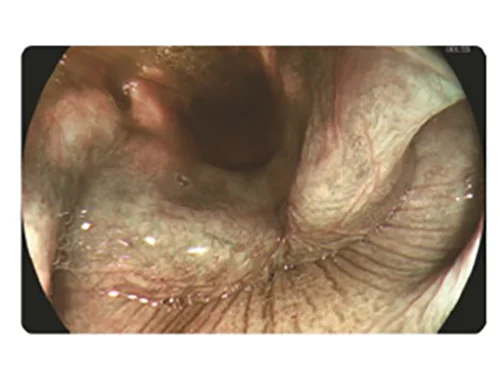

HEI

HEI: Улучшенная визуализация гемоглобина

Сочетание узкополосного красного, зеленого и желтого цветов улучшает видимость глубоких кровеносных сосудов и точек кровотечения за счет использования алгоритма слияния изображений и технологии автоматической обработки.

Применение

- Выявление кровотечений (упрощает остановку интраоперационных кровотечений)

- Визуализация варикозно расширенных вен для проведения лечения (упрощает обнаружение целевых вен при инъекционном лечении или перевязке вен).